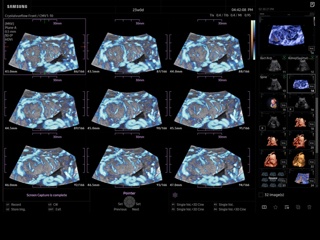

Atlas of ultrasound images - obsterics

In the section "Оbsterics" of atlas the results of ultrasonic examinations of pregnant women with different durations of gestation are represented. Here you can see images of internally organs, cerebrum, cordis and the sex of the fetus, the sonograms of multiple pregnancy, the blood flow in placenta and umbilical cord, defects of fetal`s development, etc.